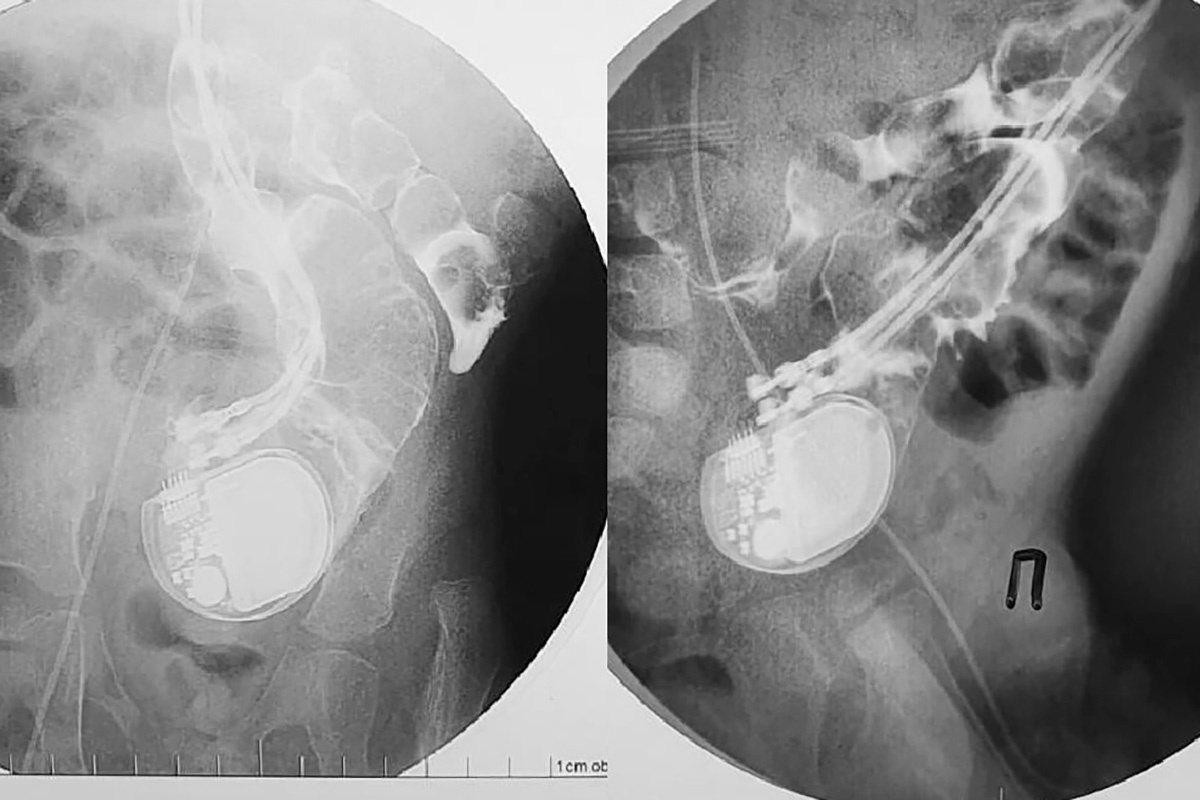

meshalkinclinic / Telegram📷Кардиостимулятор в кишечнике трехлетнего мальчика

Ребенок появился на свет с редким видом аритмии — подобная патология бывает только у одного из 25 тыс. младенцев. Поэтому в два дня от роду ему установили кардиостимулятор. Из-за миниатюрных размеров устройство прикрепили не как обычно под ключицу или в грудной клетке, а в области живота поверх брюшины и прямой мышцы, которые отделяли кардиостимулятор от брюшной полости. Электроды были установлены на правое предсердие и верхушку правого желудочка.

«На рентгенографии подтвердилось то, что казалось невероятным: устройство не только сумело мигрировать в брюшную полость, преодолев барьер из мышцы и брюшной стенки, но и проникло непосредственно в кишечник, продолжая при этом исправно работать и задавать необходимый ритм сердцу», — агентство цитирует Центр Мешалкина.

Аппарат проник в кишечник через сигмовидную кишку. Выйти из тела он не смог из-за проводов, протянутых с сердцу.